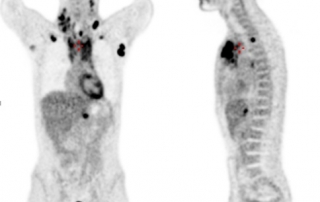

| Avant traitement | Après BEACOPP renforcé x 2 cycles Masse médiastinale dont le SUVmax est comparable au bruit de fond hépatique, correspondant à une réponse métabolique complète |

Résultat : la réponse métabolique complète après BEACOPP renforcé 2 cycles conduit à poursuivre le traitement par ABVD x 4 cycles selon l’essai AHL2011, avec évaluation après ABVD 2 cycles et en fin de traitement. La TEP-TDM montre une masse médiastinale résiduelle de taille 36 x 42 mm inchangée entre l’évaluation après 4 cycles et en fin de traitement, avec maintien de la réponse métabolique complète, correspondant à une diminution de 88%. Classement rémission complète incertaine selon les critères de Cheson 1999 et à une rémission complète selon les critères IWG 2007.